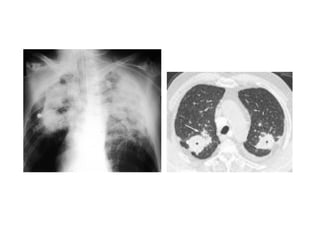

EAA: HRCT, acute disease

Hypersensitivity Pneumonitis • Animmune‐mediated granulomatous inflammatory reaction to organic antigens in the alveoli and in the respiratory bronchioles • Also called: extrinsic allergic alveolitis • Dx and etiology is often in the history HRCT in Acute HP